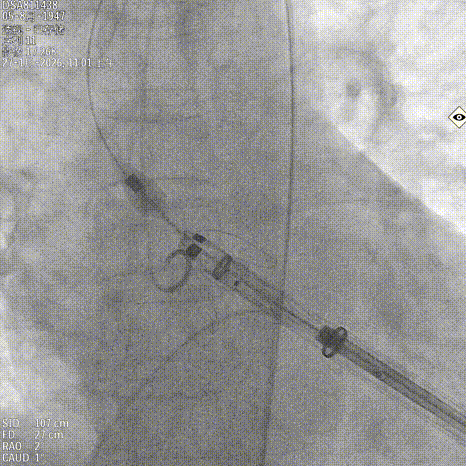

造影确认右窦居中位置

释放定位件尝试入窦

输送系统进行调弯

造影第一次未完全入窦